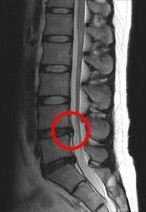

写真の赤い丸の飛び出している椎間板がヘルニアです。

腰の背骨と背骨の間にある椎間板というクッションが飛び出してしまい、足に伸びる神経を圧迫することにより、足のシビレや足に力が入らないという症状が出ます。